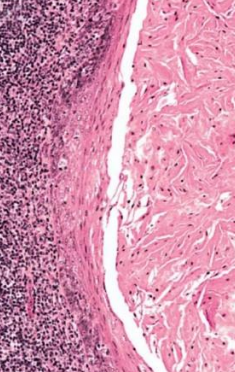

| Periapical(radicular) cysts | Rest of Malassez 被刺激 | - | - | true/ periapical cyst 圓形的光通性包圍根尖 |

牙根吸收, 2cm ↑ 根管治療無效  |

- Rest of Malassez

- Hertwig’s epithelial 殘留

- Rushton bodies

- 齒源系上皮